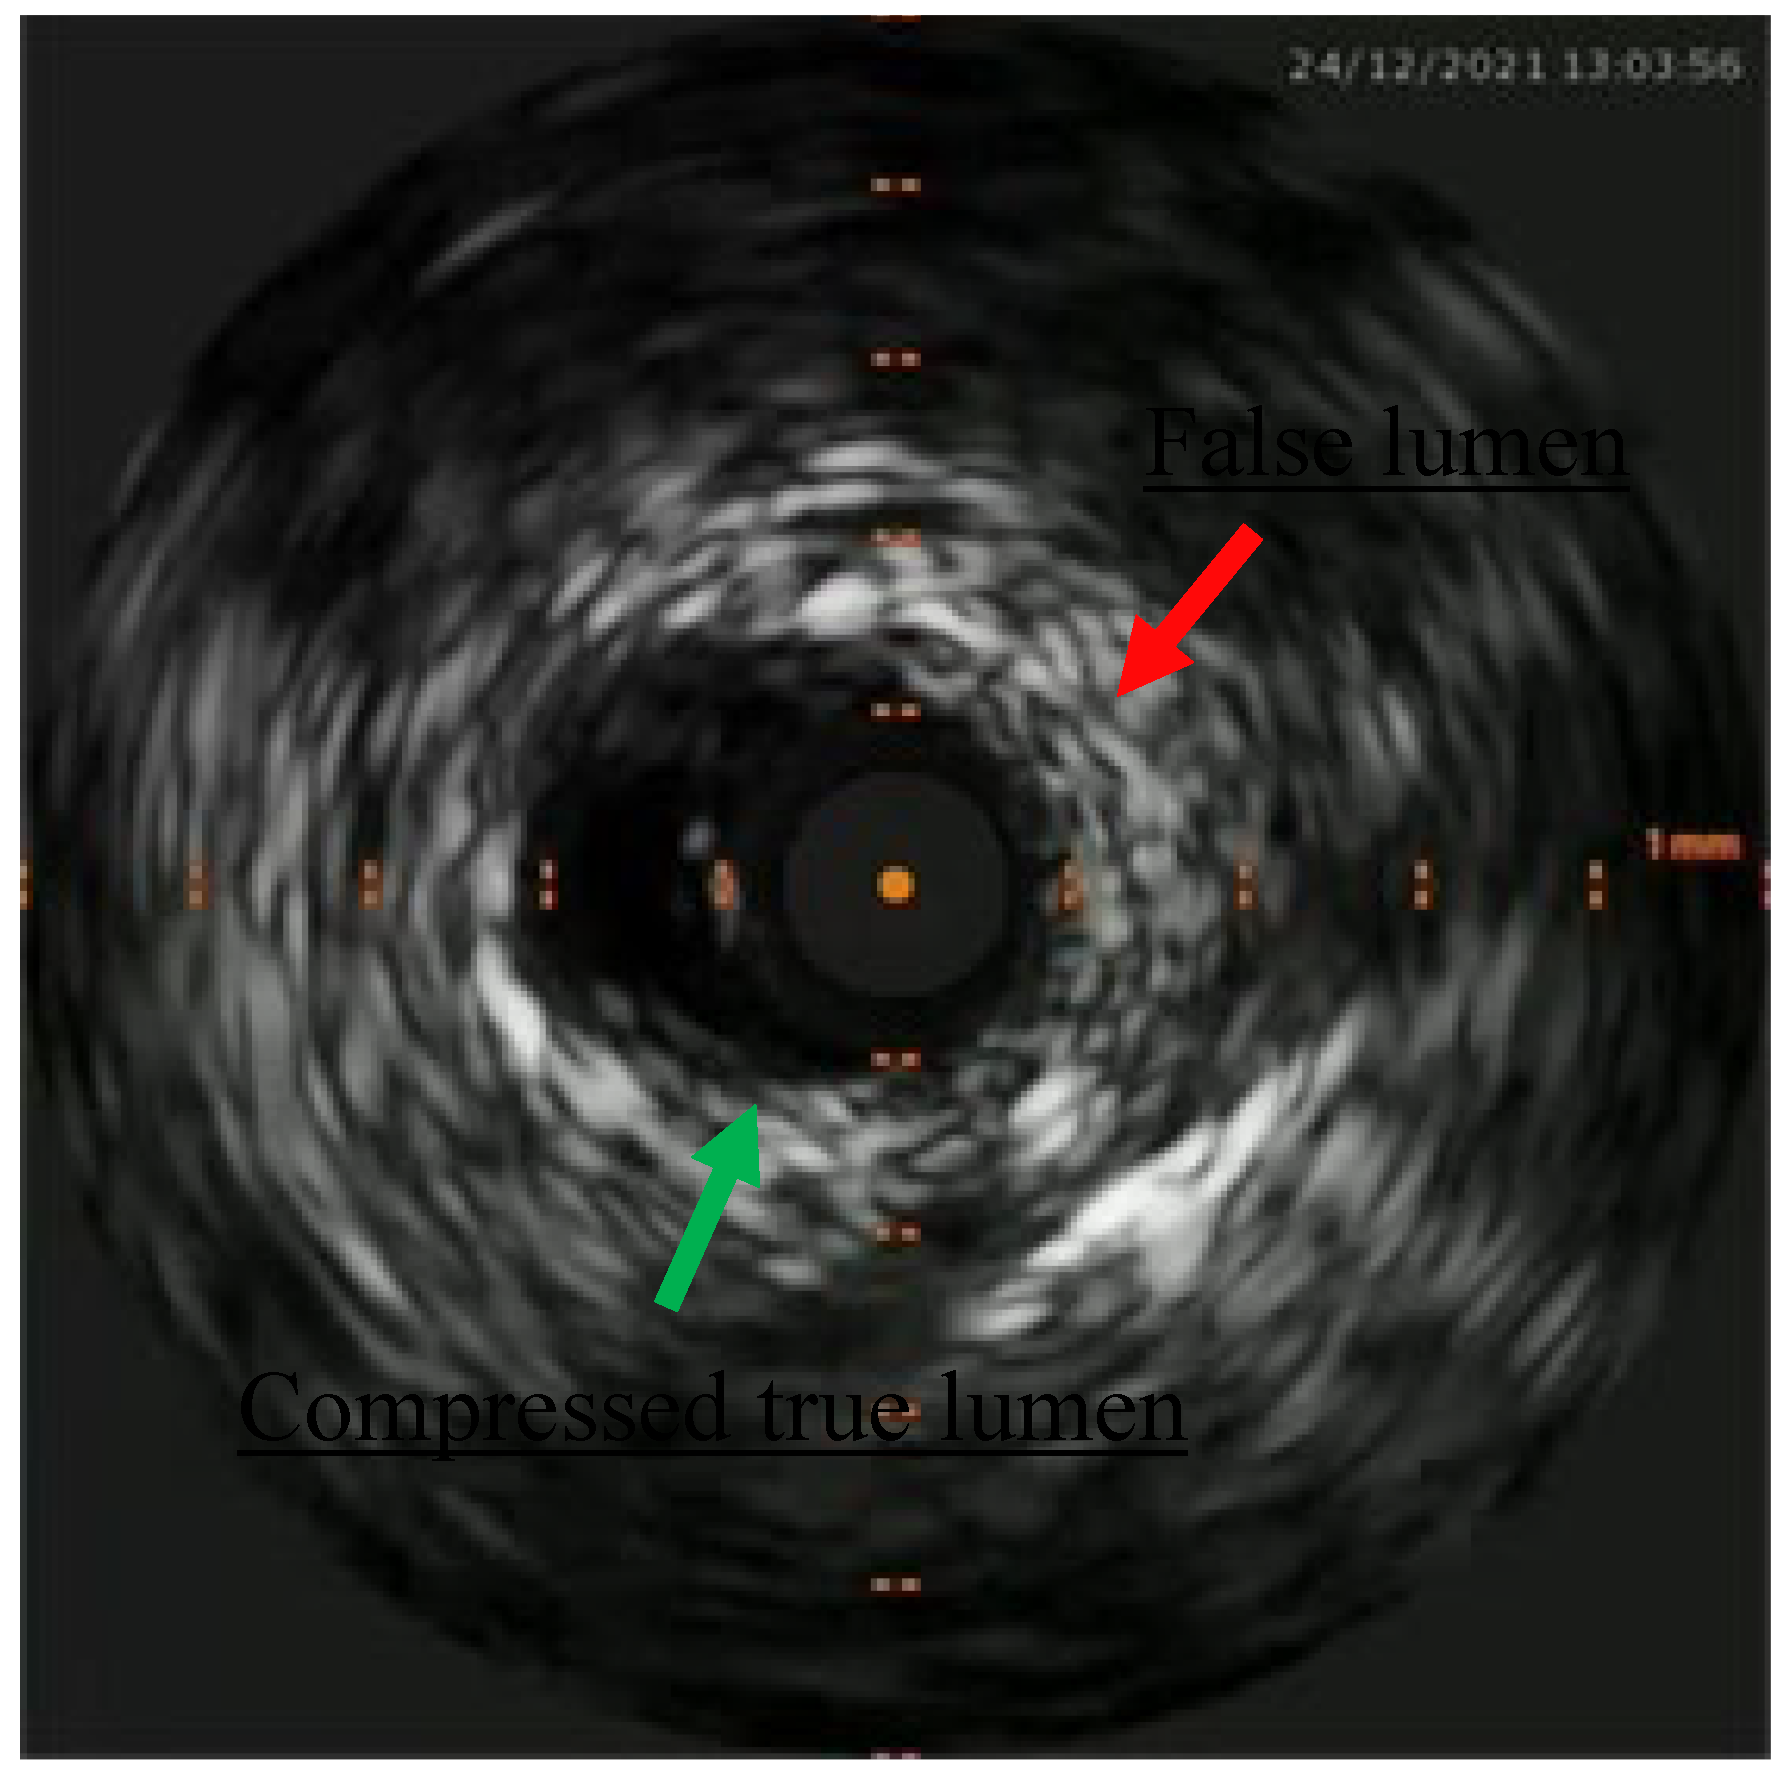

Figure 4. IVUS showing distal true lumen.

Figure 5. Short subintimal track with compressed true.

Percutaneous coronary intervention was therefore considered appropriate and a purposely undersized EBU 3.0 6F was selected. Regarding mechanical circulatory support only intra-aortic balloon pump was available. After rapid consultation, considering the insertion of the device, a decision was made to not proceed given the potential lengthening of the procedure, the need for femoral access and the issue of scanning the fetus with the XR detector. A safety wire, Terumo Runthrough floppy, was immediately placed on the patent left circumflex artery whilst after failing wiring on the left anterior descending with a Balance Middleweight wire a Sion wire was advanced up to the apical LAD. An IVUS run confirmed distal true lumen wire position showing a short subintimal track without compromise of any major side branch (Figure 2, Figure 3, Figure 4 and Figure 5).